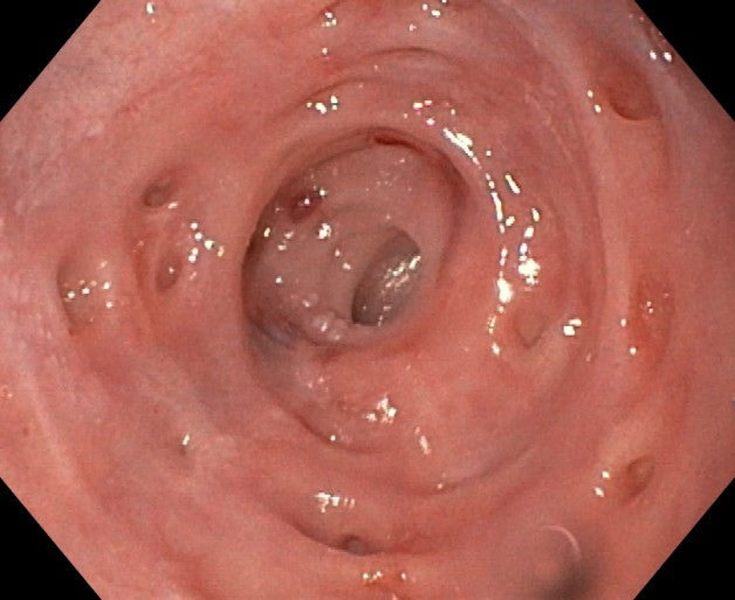

An uncommon cause of dysphagia

Fotografia